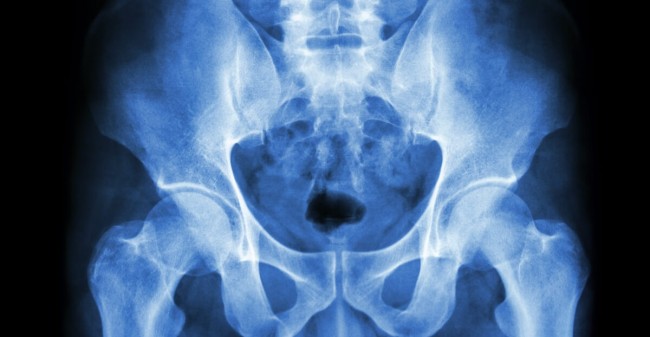

Wist je dat één op de vier vrouwen van 50 jaar of ouder last heeft van ongewild urineverlies? De veranderingen van de hormoonspiegel ten gevolge van de overgang hebben gevolgen voor de spieren van de bekkenbodem. Deze gaan namelijk vervetten en wanneer ze niet in conditie gehouden worden kunnen er problemen ontstaan met de steunfunctie van deze spier, zoals bijvoorbeeld verzakkingen met als gevolg klachten met betrekking tot verlies van urine of ontlasting, pijn bij gemeenschap of een zwaar gevoel.

Natuurlijk kun je in dat geval je toevlucht zoeken tot incontinentiemateriaal, maar daarmee worden slechts de symptomen bestreden. Beter is het om de kwaal zelf aan te pakken met incontinentietraining. Lauri Savelkoul helpt als geregistreerd bekkenfysiotherapeut veel cliënten van hun vervelende kwaal af. ‘Er rust helaas nog steeds een taboe op incontinentie. Door een gerichte training kunnen klachten echter verdwijnen of kan een operatie voorkomen worden. Met de juiste oefeningen kun je de spier versterken waardoor de steunfunctie sterker wordt. Maar ik geef ook coördinatietraining om vrouwen, bijvoorbeeld na een bevalling, weer te leren voelen. Het kan ook voorkomen dat de bekkenbodemspier juist verkrampt is en de vrouw moeite heeft met ontspannen wat pijn geeft bij het vrijen. Met relaxatietraining kan ik vrouwen leren ze hoe ze deze spierspanning kunnen loslaten.’

Spierspanning inzichtelijk maken

Een behandeling bij een geregistreerde bekkenfysiotherapeut begint met een intakegesprek. ‘Ik moet eerst weten wat er precies aan de hand is. In de volgende afspraak volgt het onderzoek om de juiste diagnose te kunnen stellen en kunnen we gaan beginnen met oefenen. Ik kan de spieractiviteit van de bekkenbodem zichtbaar maken met het myofeedbackapparaat. Via een curve op het beeldscherm van mijn laptop kan de cliënt zelf zien wat er gebeurt als ze haar bekkenbodemspier aanspant. Het komt ook vaak voor dat de cliënt niet goed weet waar deze spier zich bevindt of niet voelt hoe deze aangespannen kan worden. Dan maak ik gebruik van elektrotherapie, waardoor de spier geprikkeld wordt om de aanspanning en ontspanning te laten voelen. Dat klinkt enger dan het is hoor’, stelt Lauri gerust. ‘Het is geen naar of pijnlijk onderzoek; het geeft juist veel duidelijkheid.’